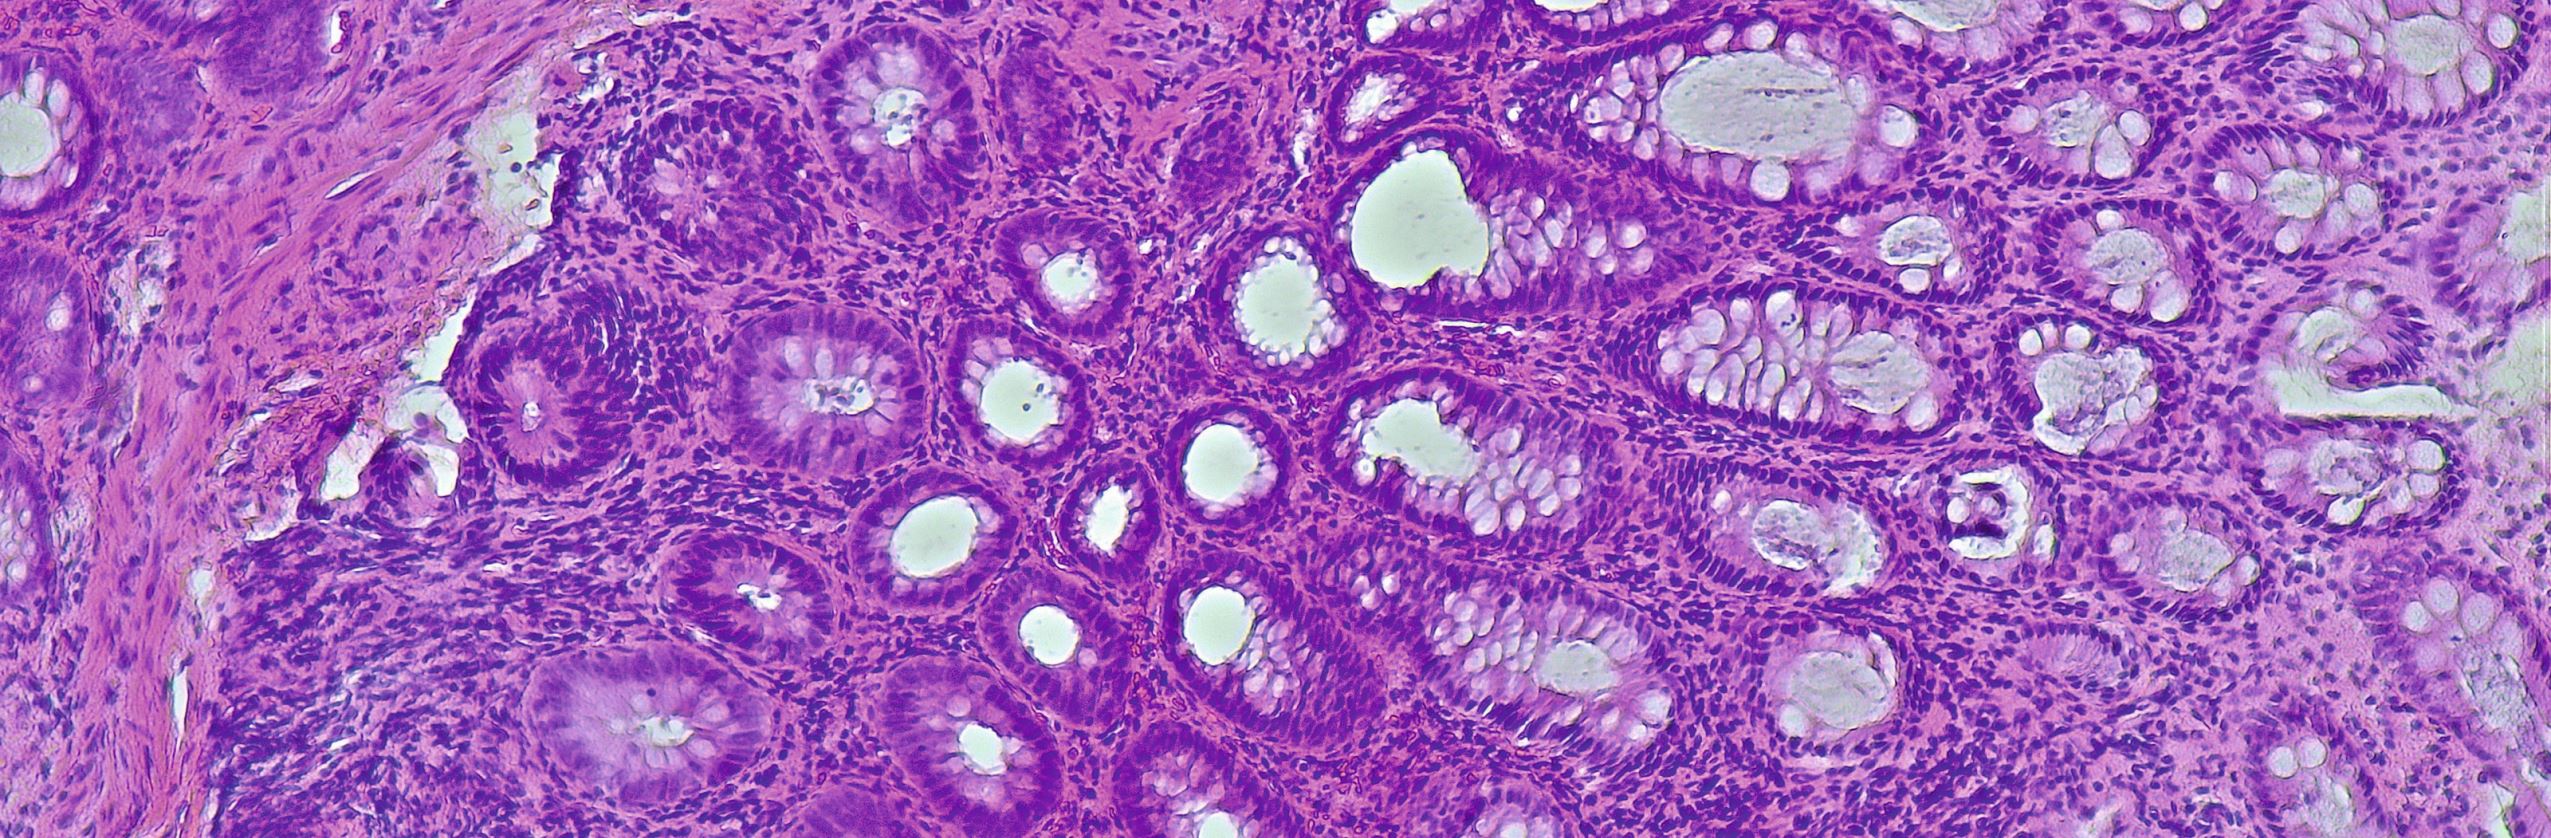

DMH / stock.adobe.com